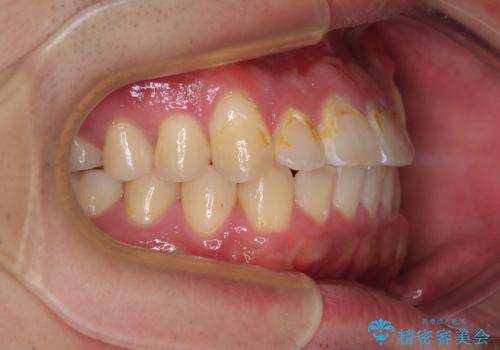

舌突出癖が改善されず、なかなか正中の隙間や上下の前歯が接触しなかったために治療が長期化してしまいました。

また、治療期間中のプラークコントロールが悪く、ブラッシング指導も奏功しなかったため、装置の周りが脱灰した状態(初期むし歯)となってしまいました。